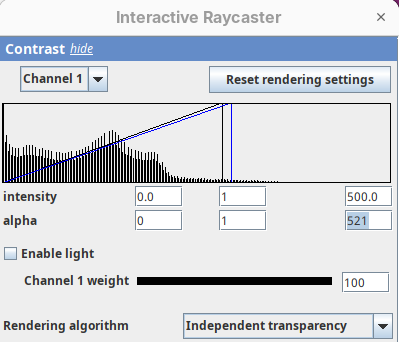

Contrast

The Contrast section shows a histogram of pixel intensities of the image for each channel, which we can choose using the dropdown menu. We can set the minimum, gamma, and maximum values for the intensity and alpha (transparency) properties of each pixel. The weight option controls the general opacity of the channel (0=invisible, 100=visible). There’s also more advanced options like lighting and rendering algorithm which we’ll simply use the default states as they are usually good for most use cases.

Adjusting the intensity and alpha values is the most impactful way to improve the 3D rendering. With the intensity setting we can define which pixel value in the image corresponds to total black (minimum) and which corresponds to total white. It’s the same as in the standard Brightness & Contrast tool. By default, 3Dscript will load these values from the original stack. In this case, it loaded min=3 and max=521.

Let’s change these values to see how it impacts the 3D rendering.

- Change the intensity minimum to

250.

You will see that the darkest parts of the rendering will become even darker and no longer visible. We are losing real information from the data; we do not want that.

- Set the

minto0, for now. - Then, change the

maxto250.

The brightest parts of the rendering will become all white. It is so bright that we can no longer resolve details of the surface. We are losing information and also do not want that.

- Set the

maxto500.

Note that when you change an intensity value, the min/max black line in the histogram moves. You can also grab the line and move it manually to change the values.

The blue line represents the alpha values. In 3D rendering, a pixel has a transparency value linked to its intensity. The alpha min defines the value for full transparency and the max the value for full opacity.